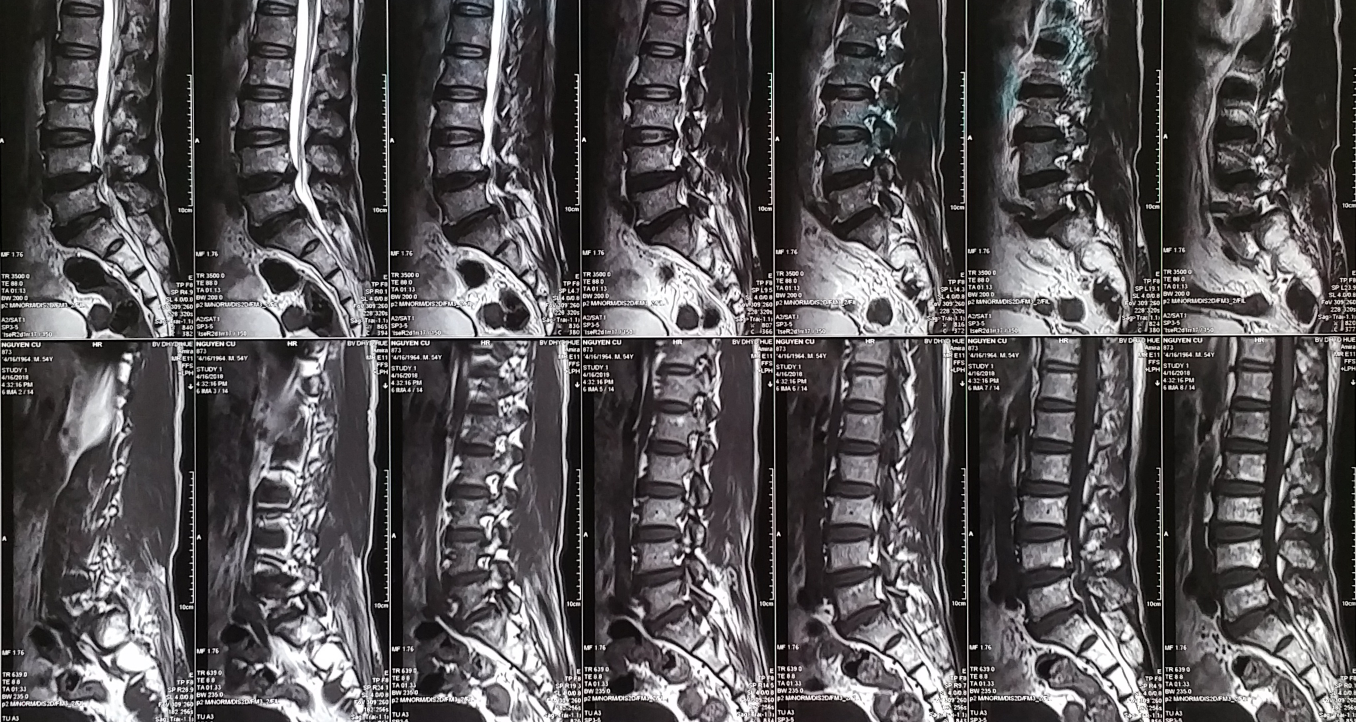

Chụp cộng hưởng từ MRI (Magnetic Resonance Imaging) là kỹ thuật Chẩn đoán hình ảnh được xem như một trong những phát minh có tính cách mạng trong kỹ thuật y học, sử dụng từ trường và sóng radio. Hình ảnh chụp cộng hưởng từ MRI có độ tương phản cao, chi tiết giải phẫu tốt cho phép phát hiện chính xác các tổn thương hình thái, cấu trúc các bộ phận trong cơ thể được thăm khám. Khả năng tái tạo hình ảnh 3D tốt, không có tác dụng phụ nên ngày càng được chỉ định rộng rãi cho nhiều ứng dụng chuyên khoa khác nhau.

3. Mục đích chụp cộng hưởng từ cột sống thắt lưng

Chụp cộng hưởng từ cột sống thắt lưng có thể bộc lộ các nhóm bệnh lý sau:

- Chẩn đoán các bệnh lý như thoái hóa, thoát vị đĩa đệm, đánh giá Chèn ép tủy sống, rễ thần kinh.

- Đánh giá các bất thường về giải phẫu, các bệnh lý bẩm sinh liên quan đến cột sống thắt lưng

- Chẩn đoán các vấn đề khác như u cột sống, chẩn đoán di căn cột sống ở giai đoạn sớm.

- Chẩn đoán các bệnh lý trong ống sống như u trong ống sống, tụ máu.

- Chẩn đoán các bệnh lý tủy sống như u tủy, viêm tủy, bệnh lý chất trắng tủy